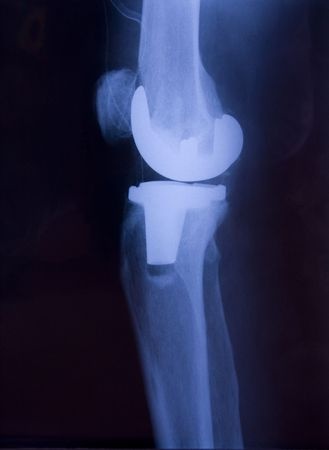

Minimally Invasive Surgery - Minimally invasive knee replacement surgery involves the removal and replacement of an affected knee joint through a smaller incision than traditional total open knee replacement surgery. The surgeon replaces the diseased or damaged knee joint with a prosthetic joint, made to mimic the function of a natural knee. Prosthetics have been engineered to feel as natural as possible, and are made with only biocompatible materials to ensure comfort and support. Using current techniques, 90% to 95% of minimally invasive knee replacement surgeries last more than 15 years.